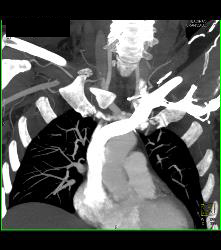

Cervical Rib With Occlusion of the Right Subclavian Artery- See Full Sequence